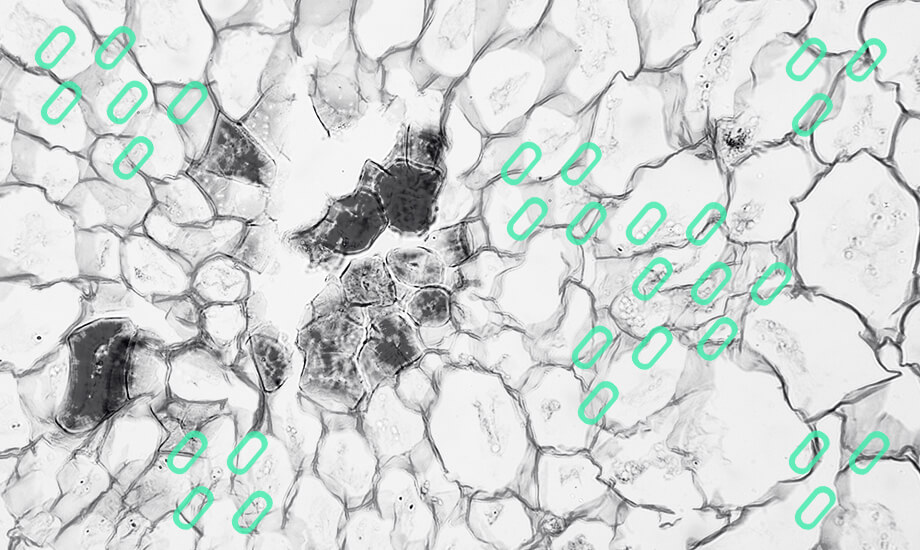

Самый сложный пункт из обсуждаемых. Фибробласты, в отличие от всех предыдущих продуктов, – действительно полноценные клетки. Именно фибробласты делают очень много полезного для красоты нашей кожи. Они активно синтезируют элементы внеклеточного матрикса, в том числе коллаген и эластин. Но самое интересное – фибробласты действительно очень похожи морфологически (по форме в культуре) на одни из стволовых клеток – мезенхимальные мультипотентные или стромальные. Существует целый ряд работ о схожести мезенхимальной клетки и фибробласта. И действительно, эти типы клеток имеют общее происхождение, экспрессируют почти идентичный набор поверхностных маркеров и демонстрируют много общих свойств в культуре. Однако это может объясняться и некоторой «унификацией» культивируемых вне организма клеток (ведь их исследуют, предварительно изъяв из естественной «среды обитания»), и недостаточно точными способами оценки характеристик клеток. Кроме того, существует мнение, что мезенхимальная стволовая клетка и фиброцит (самый зрелый фибробласт) – это крайние точки в очень разноплановой популяции клеток, среди которых много промежуточных форм разной степени дифференцировки. Следует учитывать, что важную роль играет место получения клеток для использования. Мультипотентная мезенхимальная клетка во взрослом организме может существовать в специальных нишах с особыми условиями, а фибробласт, как одна из самых популярных клеток в нашем организме, присутствует в очень многих органах, в том числе в большом количестве – в коже. Эта тема требует отдельного обсуждения, но сейчас стоит отметить, что в коже фибробласты имеют свои конкретные задачи: изготовление межклеточного матрикса, участие в процессах воспаления, заживления ран, взаимодействие с другими клетками. Поэтому когда речь идет о применении аутологичных (своих) фибробластов, полученных из кожи и для восстановления состояния кожи, отождествлять эту процедуру с терапией стволовыми клетками всё же некорректно. Важным моментом является большой опыт безопасного применения аутологичных дермальных фибробластов в клиниках США, РФ, а позже и других стран, в том числе Украины. Это один из очень немногих официально одобренных в мире непосредственно клеточных продуктов. Исходя из описанного выше, говорить об «инъекциях стволовых клеток» не стоит.